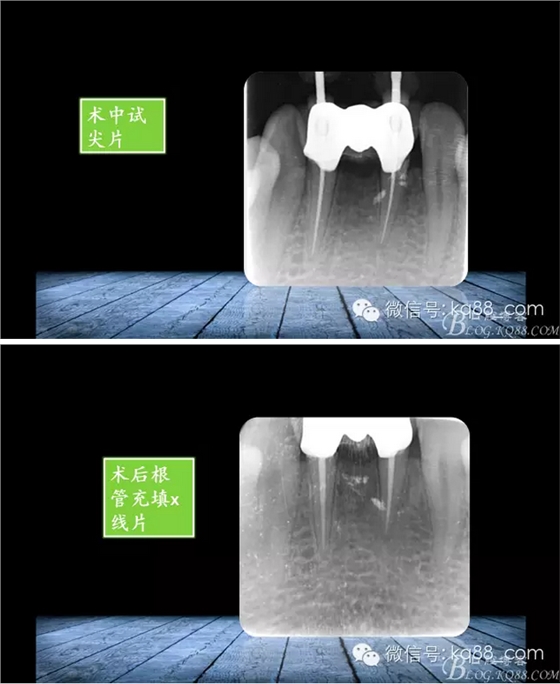

QQ圖片20150817140633.png

QQ圖片20150817140707.png